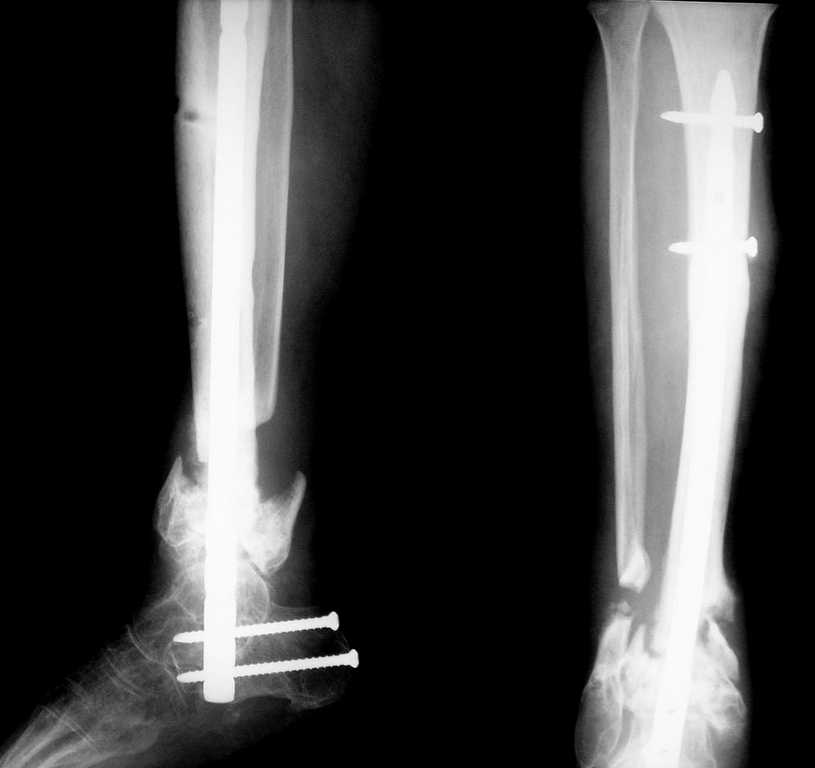

[Ortho] Ложный сустав н/3 голени

Вот что в итоге получилось. Вопрос по поводу нагрузки: может сразу дать? и зря я поставил

статический винт?